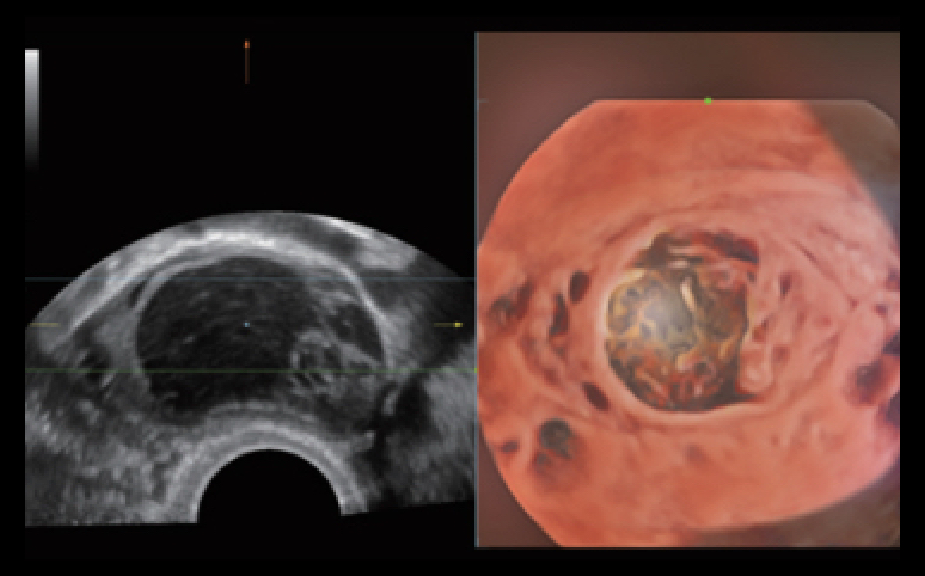

De Nuewa I9, speciaal ontworpen voor vrouwen en neonatale gezondheidszorg, biedt een innovatieve ervaring van binnenuit. Deze innovaties zijn ontwikkeld op basis van diepgaande inzichten in complexe klinische scenario's en bieden nauwkeurige en tijdige antwoorden, evenals een uitstekende effici?ntie en opmerkelijke gebruikerservaring.

Full-stack oplossing aangedreven door ZST+

Het ZST+ platform is een buitengewone innovatie en revolutie in de wereld van ultrasound. Het transformeert ultrasoundgegevens van conventionele bundelvorming naar kanaalgegevensverwerking. Het overwint de traditionele afweging tussen ruimtelijke resolutie, temporele resolutie en weefseluniformiteit, en levert een uitzonderlijke beeldkwaliteit voor oneindige beeldvormingsoplossingen met non-stop verbeteringen.